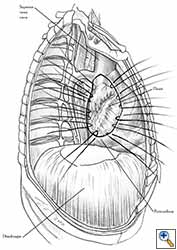

Pericardioplasty is also indicated for pericardial defects resulted after harvesting the pericardium to cover the bronchial stump after pneumonectomy (Figures 2a, 2b) [3]. Similarly, other defects that result after harvesting a pericardial graft for various purposes may need prophylactic reconstruction.

Video 1 depicts a pericardial reconstruction with Marlex after a right completion pneumonectomy with pericardiectomy for lung adenocarcinoma (see also Figure 1). The technique of pericardial reconstruction after the resection of invasive mediastinal tumours is illustrated in Figures 8a-c). Video 2 depicts a pericardial reconstruction with Mersilene mesh after the resection of a malignant thymoma invading the anterior pericardium (see also Figure 4b). The technique of right pericardial reconstruction after extrapleural pneumonectomy is illustrated in Figures 9a and 9b). Video 3 depicts a pericardial reconstruction using Gore-Tex Dual Mesh after a left extrapleural pneumonectomy (see also Figure 3). Care must be taken to prevent constriction (Figure 10).